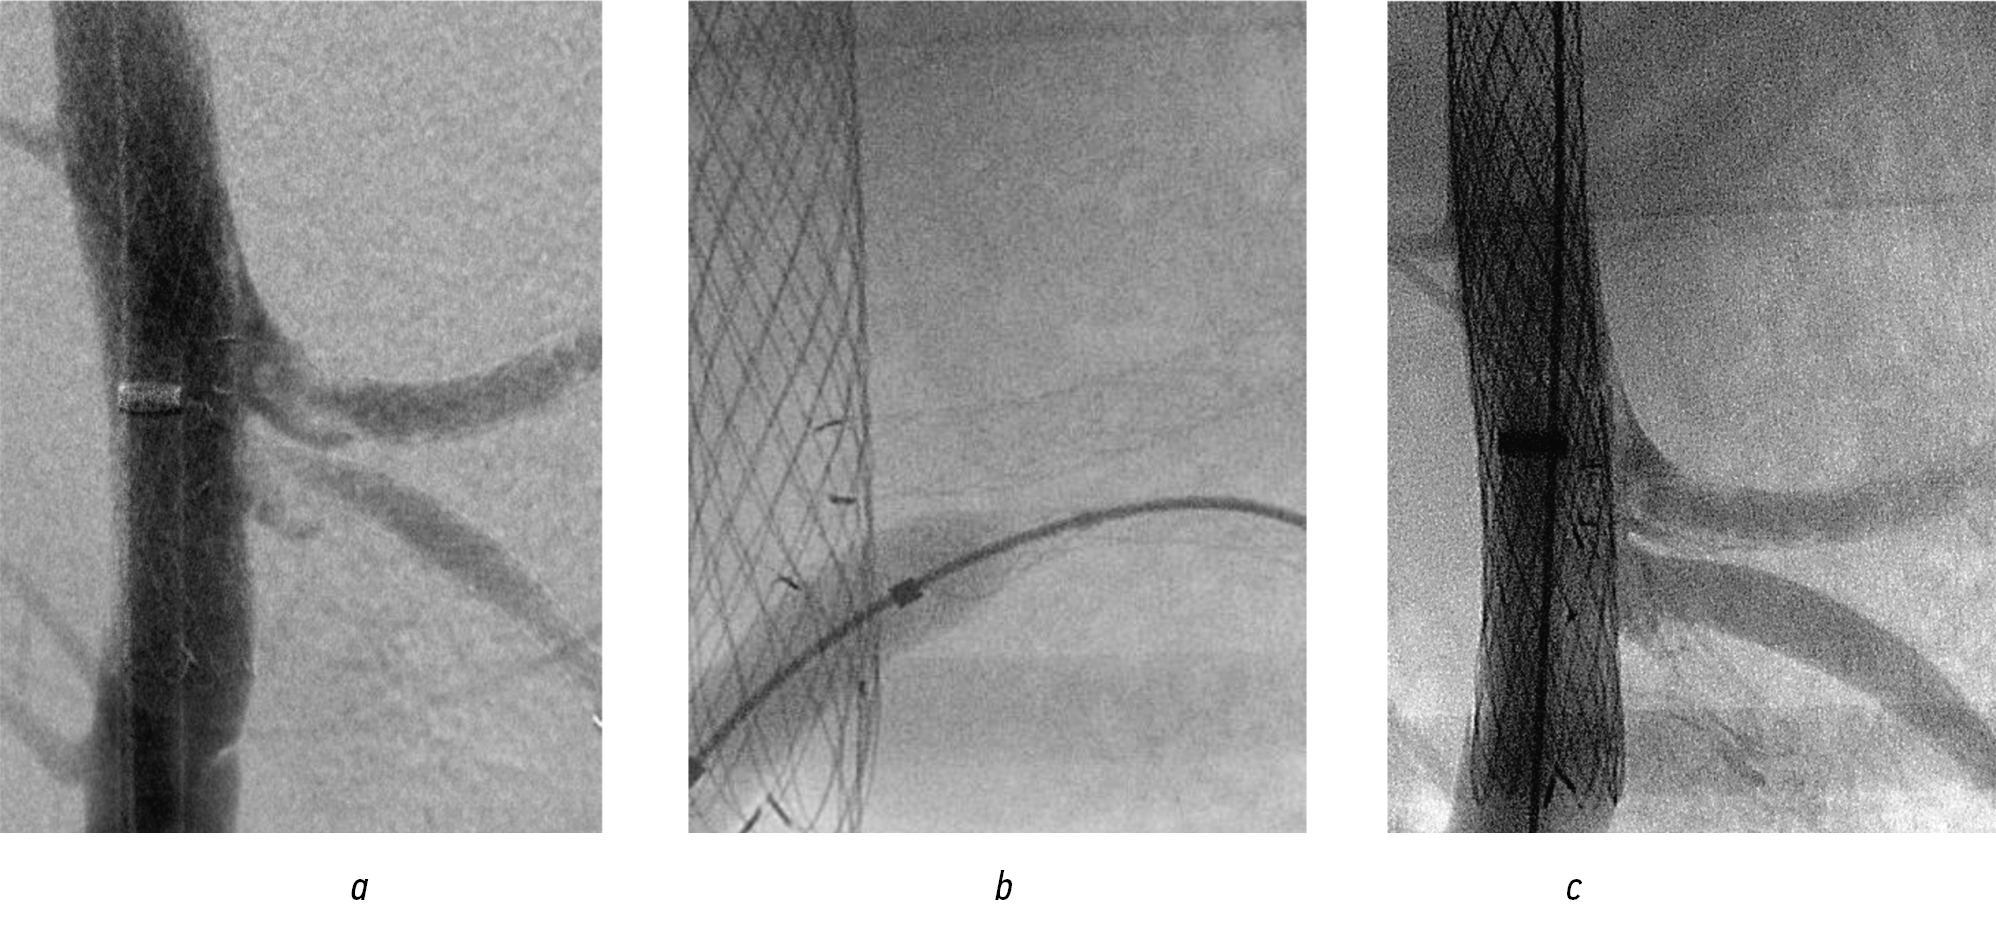

Endoprosthesis replacement of the suprarenal abdominal aorta. Under X-ray control, along a guidewire, the main trunk of a universal stent graft was implanted into the site of origin of the celiac trunk and superior mesenteric artery (Fig. 14, a). During control aortography with heparin, the orifices of the visceral branches, blocked by the installed stent, were clearly visualized (Fig. 14, b), which created the RoadMap mask.

Fig. 14. Endoprosthetics of the suprarenal aorta: а — implantation of the main trunk; b — control angiogram

Alternately, personalized fenestration of the graft wall was performed in the projection of the orifices of the celiac trunk and superior mesenteric artery. Balloon dilatation of the fenestrated openings was subsequently performed with the implantation of lead modules into the visceral branches (Figs. 15 and 16). After their installation, dilatation with a balloon catheter was mandatory. In the control image, the structure was passable, and the visceral branches were clearly contrasted without signs of residual stenosis in the fenestrated area (Fig. 17).

Fig. 15. Branching of the ventral trunk mouth: а — personalized fenestration over the ventral trunk mouth; b — balloon dilatation of fenestration; c — implantation of visceral branching

Fig. 16. Stages of endoprosthetics in the suprarenal aorta (continued): а — personalized fenestration over the mouth of the superior mesenteric artery; b — balloon dilation of the fenestration opening; c — implantation of the module into the superior mesenteric artery